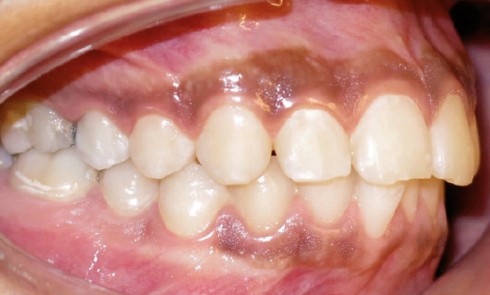

Examen initial Âgée de 15 ans, cette patiente est adressée par son chirurgien-dentiste pour un avis orthodontique car une décision...